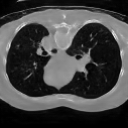

The results presented in Table 1 and 2 show our proposed method’s performance on unconditional 3D brain MR and chest CT image generation. Our proposed approach not only outperforms most comparing methods in FID and MS-SSIM metrics, it also has the lowest inference GPU memory footprint at a resolution of and was the only diffusion-based method that could be trained at a resolution of . Operating in the wavelet domain and profiting from the reduced spatial dimension also results in a relatively short inference time of / at the respective resolutions. Compared to the results presented in [23], we did not find that incorporating wavelet information into the network’s feature space (WavU-Net) increased the model’s performance. Qualitative results of our proposed method (WDM) are shown in Fig. 2 and 3. A qualitative comparison of samples produced by all evaluated methods can be found in the Supplementary Material.